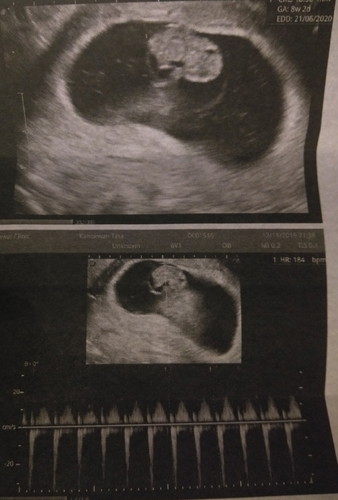

วันนี้ไปหาคุณหมอหมอบอกอายุครรภ์8 วีค2วันแล้วค่ะ?